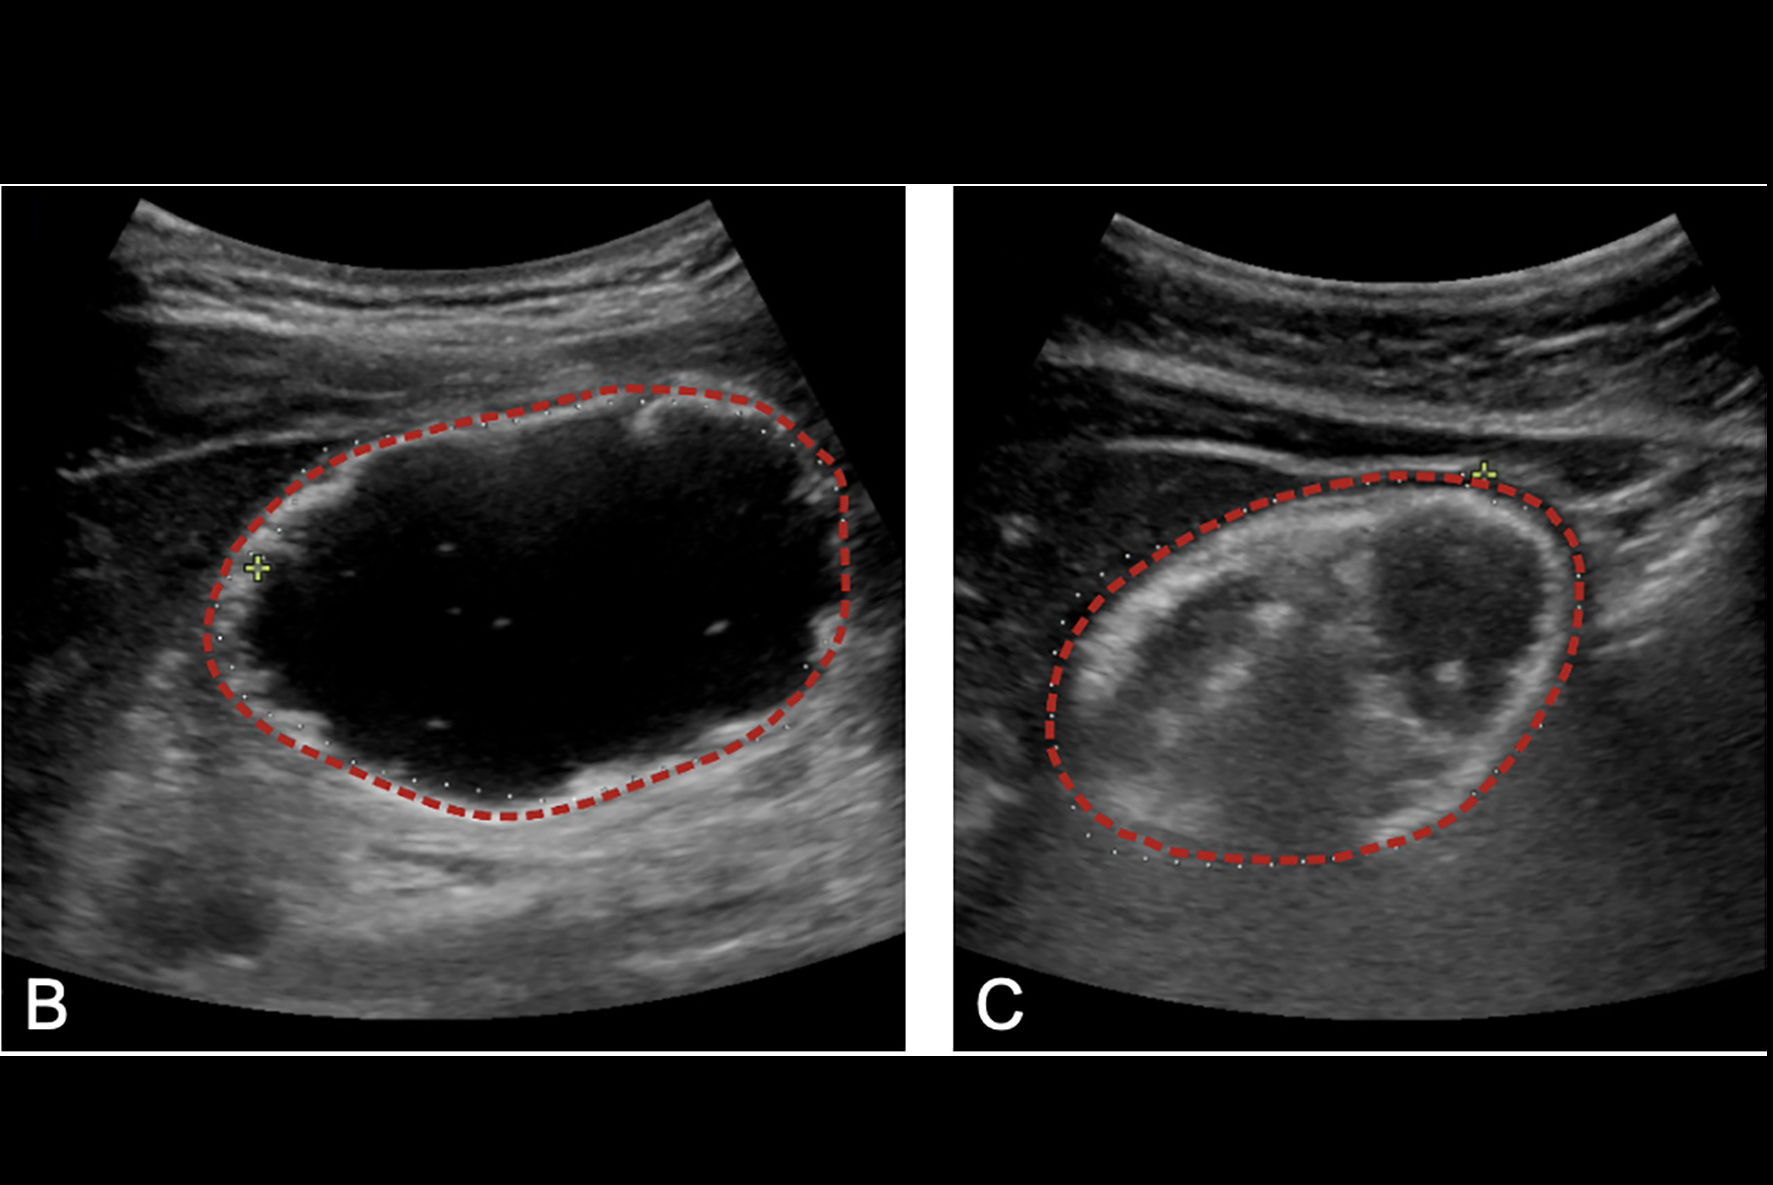

The researchers suggested that the PAS score could be used to create an imaging pathway. While ultrasound is easier to access than MRI and doesn’t use radiation, incomplete visualization can lead to more imaging workup and more time spent in the emergency department.

Turpin and colleagues sought to improve ultrasound’s performance to position the modality for first-line imaging for all patients. In 2022, the team reviewed appendix ultrasound exams performed in 2020. It identified scanning technique and ambiguity in the reporting of findings as major contributors to subpar ultrasound performance. Sonographers underwent training that focused on bowel and appendix imaging.

The team created a standardized template for ultrasound and MRI, adapting the imaging pathway so that all PAS levels underwent ultrasound first. The group focused the study on whether MR imaging was needed after ultrasound and how the pathway affected clinical team time (time from patient being placed in an emergency department room to disposition).